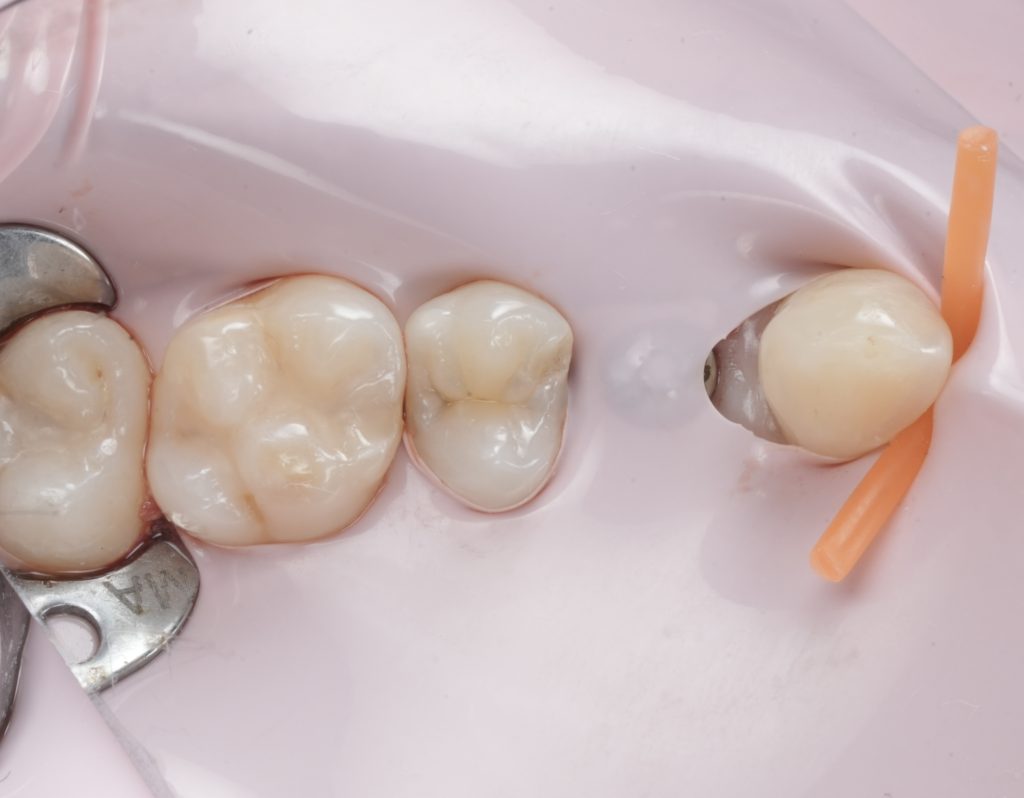

Images to place

- Fig. 12: Immediate post-op occlusal (dam still on).

- Fig. 13: Post-op occlusal after polish (dam off).